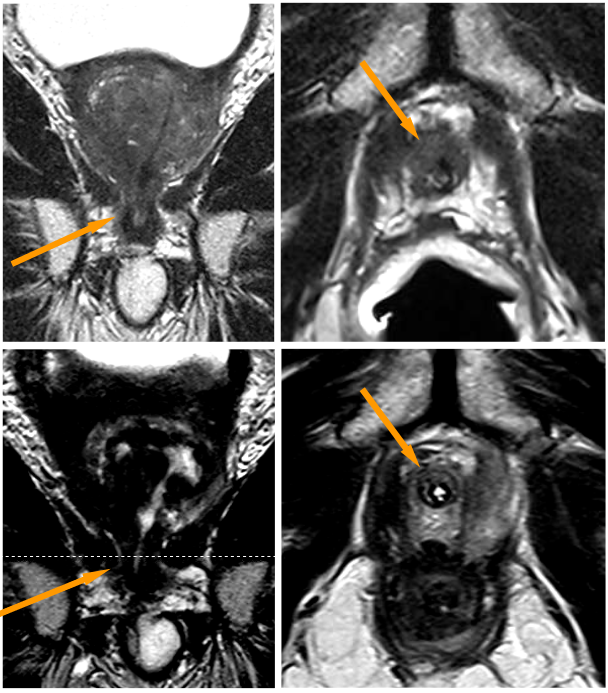

Abbildung 3 zeigt die Behandlung eines Prostatakarzinoms Stadium T4, N0, M0, Gleason-Score 8, bei einem 79-jährigen Mann mit Infiltration des Enddarmes (Rektums; gelbe Pfeile oben). Eine radikale Prostatektomie wäre nur mit zusätzlicher Entfernung des Rektums und Anlage eines künstlichen Darmausganges (Anus praeter) möglich gewesen.

Die Infiltration des Enddarmes ist auf den MRT-Bildern in der oberen Reihe der Abbildung Z abgebildet: Links: seitliche (sagittale) Aufnahme; Mitte: Querschnitt (axiale Aufnahme) mit T2-Wichtung; Rechts: Querschnitt (axiale Aufnahme) nach Kontrastmittelgabe.

Die untere Bildreihe zeigt die Verhältnisse 9 Monate nach der IRE-Behandlung: Die Wand des Enddarmes stellt sich normal, ohne Verletzung und ohne Fistel (Fehlverbindung) zur Prostata dar: Links: seitliche (sagittale) Aufnahme; Mitte: Querschnitt (axiale Aufnahme) mit T2-Wichtung; Rechts: Querschnitt (axiale Aufnahme) nach Kontrastmittelgabe.